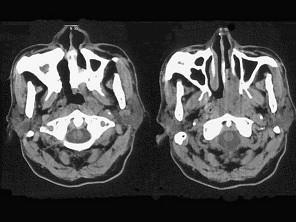

问题 男,64岁,间断性流鼻血一年余,近1个月加重,CT如图所示,最可能的诊断为 ( )

选项 A、鼻咽部淋巴组织增生 B、鼻咽癌 C、鼻咽纤维血管瘤 D、鼻咽部恶性淋巴瘤 E、鼻咽部腺样体增生

答案 B